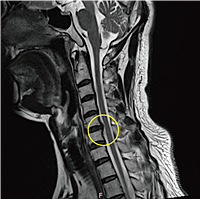

목디스크 증상 11가지 치료방법에 대해 알고 계신가요? 목디스크는 현대인에게 흔히 발생하는 질환 중 하나로, 목과 어깨, 팔 등에 통증을 유발할 수 있습니다. 디스크가 목뼈 사이에서 탈출하거나 손상되면서 신경을 압박하는데, 이는 일상생활에 큰 불편함을 초래할 수 있습니다. 이 글에서는 목디스크의 주요 증상 11가지와 함께 효과적인 치료 방법에 대해 알아보겠습니다. 목디스크로 고통받고 있는 분들에게 이 글이 도움이 되길 바랍니다.

9. 수술

목디스크 증상이 심각하거나 다른 치료 방법으로 호전되지 않는 경우, 수술이 필요할 수 있습니다. 디스크를 제거하거나, 손상된 부위를 수술을 통해 복구할 수 있습니다. 수술은 최후의 수단으로 고려되며, 전문 의사와 상담하여 결정해야 합니다.